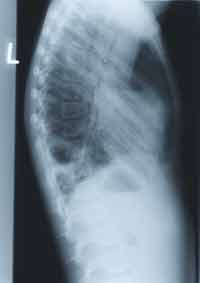

She had a bronchoscopy and bronchoalveolar lavage in April 1998. The lavage was cloudy, and blood-tinged in appearance. No cell count was available. There were secretions in the RUL. Cultures were negative for viruses, bacteria and fungal stains. Her clinical status improved so she was discharged home on oxygen at 2 L/min with additional planned investigations at follow-up.At follow-up, she continued to be hypoxemic on room air. Her cardiac evaluation (echocardiogram and EKG) was normal. The interval chest xray was worse although she only required oxygen at night. Follow-up in October 1998 (6 months after presentation), she was noted to have mild clubbing on examination. Interestingly, her father was also noted to have clubbing but no respiratory symptoms.

Pulmonary function tests: uninterpretable (first attempt), blood work was normal, oximetry showed that she was hypoxemic at rest, worse with exercise. One could argue about the need for a high resolution CT scan to delineate the pathology further. However, it was not done at this point.BELOW, CHEST X-RAY from October 1998.

WHAT ARE YOUR FINDINGS. WHAT WOULD YOU DO NEXT?